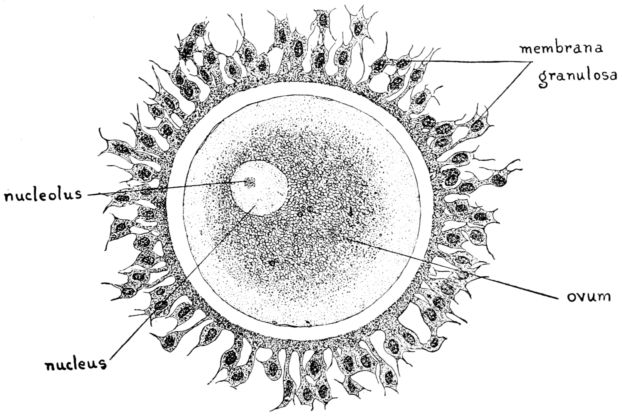

16. Diagram of human ovum 47